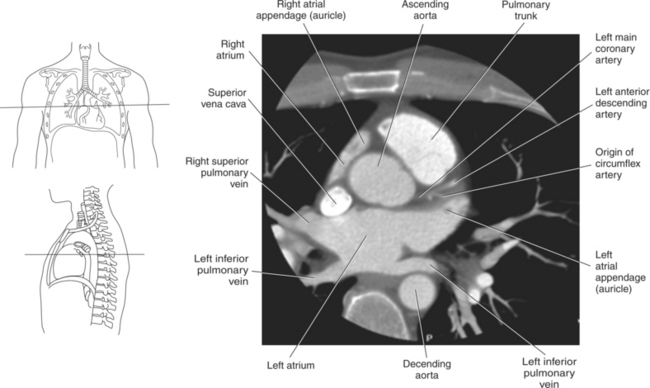

The right atrium forms the right border of the heart and receives deoxygenated blood from the body via the superior and inferior venae cavae and from the coronary sinus and cardiac veins that drain the myocardium. A small muscular embryonic appendage, the right auricle, projects upward and toward the left from the right atrium, covering the root of the aorta (Figure 6.40). The right ventricle lies on the diaphragm and comprises the largest portion of the anterior surface of the heart. It receives deoxygenated blood from the right atrium and forces it into the pulmonary trunk for conveyance to the lungs. Projecting off the inferior surface of the ventricular walls are conical-shaped projections of cardiac muscle called papillary muscles that anchor the cusps of the tricuspid valve to the right ventricle (Figure 6.39). The left atrium lies posterior to the right atrium and is the most posterior surface of the heart. It also has an embryonic appendage, the left auricle, that projects to the left of the pulmonary trunk over the superior surface of the heart. The left atrium receives oxygenated blood directly from the lungs via the four pulmonary veins (two on each side). The left ventricle forms the apex, left border, and most of the inferior surface of the heart. It receives oxygenated blood from the left atrium and pumps it into the aorta for distribution throughout the systemic circuit. The myocardium of the left ventricle is normally three times thicker than that of the right ventricle, reflecting the force necessary to pump blood to the distant sites of the systemic circulation (Figures 6.41 through 6.52). Two papillary muscles project from the ventricular walls to anchor the bicuspid valve to the ventricle (Figures 6.39 and 6.47).

Blood travels to and from the heart through the great vessels, which include the aorta, pulmonary arteries and veins, and superior and inferior venae cavae (Figures 6.54 and 6.55). The aorta is the largest artery of the body and can be divided into the ascending aorta, aortic arch, and descending aorta. The ascending aorta begins at the base of the left ventricle at the level of the sternal angle, then curves superiorly and posteriorly as the aortic arch over the root of the left lung. The top of the aortic arch is approximately at T3 (Figures 6.56 and 6.57). The arch continues as the descending aorta posterior to the left bronchus and pulmonary trunk, on the left side of the vertebral body of T4 (Figures 6.58 and 6.59). The descending aorta passes slightly anterior and to the left of the vertebral column as it descends through the thoracic and abdominal cavities (Figure 6.60). While in the thoracic cavity, the descending aorta is commonly called the thoracic aorta, and while in the abdominal cavity, it is called the abdominal aorta. The pulmonary trunk is the origin of the right and left pulmonary arteries and lies entirely within the pericardial sac. It arises from the right ventricle and ascends in front of the ascending aorta, courses posteriorly and to the left, where it bifurcates at the level of the sternal angle (T4) into the right and left pulmonary arteries (Figures 6.61 through 6.63). The pulmonary trunk is attached to the aortic arch by a fibrous cord called the ligamentum arteriosum, the remnant of an important fetal blood vessel (ductus arteriosus) that links the pulmonary and systemic circuits during fetal development (Figures 6.54 and 6.61). The right pulmonary artery courses laterally, posterior to the ascending aorta and superior vena cava, and anterior to the esophagus and right mainstem bronchus, to the hilum of the right lung. At the root of the right lung, the right pulmonary artery divides into two branches, with the lower branch supplying the middle and inferior lobes and the upper branch supplying the superior lobe (Figures 6.61 through 6.64). The left pulmonary artery, shorter and smaller than the right, is also the most superior of the pulmonary vessels. It travels horizontally, arching over the left mainstem bronchus, and enters the hilum of the left lung just superior to the left mainstem bronchus (Figures 6.61 through 6.64). Within the lungs, each pulmonary artery descends posterolateral to the main bronchus and divides into lobar and segmental arteries, continuing to branch out and to follow along with the smallest divisions of the bronchial tree (Figures 6.61 and 6.64). Located inferior to the pulmonary arteries are the four pulmonary veins, two each (superior and inferior) extending from each lung to enter the left atrium (Figures 6.54, 6.55, 6.61, and 6.64 through 6.68). They commence in a capillary network along the walls of the alveoli, where they are continuous with the capillaries of the pulmonary arteries. The venous capillaries merge to form small vessels that unite successively to eventually form a single trunk for each lobe: three for the right and two for the left lung. Frequently the trunk from the middle lobe of the right lung unites with the trunk from the upper lobe, forming just two trunks on the right side prior to entering the left atrium. The right superior pulmonary vein collects blood from the upper lobe segments of the right lung and passes anterior and inferior to the right pulmonary artery, behind the superior vena cava. The right inferior pulmonary vein receives blood from the right lower lobes of the lung and crosses behind the right atrium to the left atrium (Figures 6.61 and 6.69 through 6.71). The left superior pulmonary vein receives blood from the left upper lobe of the left lung and courses anterior and inferior to the left main bronchus as it enters the left atrium. The left inferior pulmonary vein drains the inferior lobe of the left lung and passes toward the left atrium anterior to the bronchi (Figures 6.61 and 6.72 through 6.74). The pulmonary veins course more horizontally than the pulmonary arteries and are ultimately oriented toward the left atrium. At the root of the lungs, the pulmonary veins are anterior to the pulmonary arteries, which are anterior to the bronchus. While within the lungs, the branches of the pulmonary arteries are anterior to the bronchi, which are anterior to the pulmonary veins. The superior and inferior venae cavae are the largest veins of the body. The superior vena cava is formed by the junction of the brachiocephalic veins, posterior to the right first costal cartilage, and carries blood from the thorax, upper limbs, head, and neck (Figure 6.24). As it travels inferiorly, it is located posterior and lateral to the ascending aorta before entering the upper portion of the right atrium (Figures 6.54 through 6.59). The inferior vena cava is formed by the junction of the common iliac veins in the pelvis and ascends the abdomen to the right of the abdominal aorta and anterior to the vertebral column. It passes through the caval hiatus of the diaphragm and almost immediately enters the inferior portion of the right atrium (Figures 6.75 and 6.76).

Figure 6.59 Axial CT scan of chest with ascending and descending aorta.

Key: SVC, Superior vena cava; asa, ascending aorta; da, descending aorta; ca, carina;

The two main coronary arteries are the first vessels to branch off the ascending aorta (Figures 6.91 and 6.92). The right coronary artery arises from the base or root of the aorta (right aortic sinus) and passes anteriorly between the pulmonary trunk and right atrium to descend in the coronary (atrioventricular) groove. As it reaches the diaphragmatic surface, it gives off a right marginal branch that runs toward the apex of the heart. The right coronary artery then turns to the left and enters the posterior interventricular groove, where it gives off the posterior interventricular branch (posterior descending artery). The posterior interventricular branch continues to descend along the interventricular groove toward the apex, where it anastomoses with the left anterior descending artery of the left coronary artery. The right coronary artery and its branches supply the right atrium, right ventricle, interventricular septum, and the sinoatrial (SA) and atrioventricular (AV) nodes. It also supplies a portion of the left atrium and ventricle (Figures 6.92 through 6.96). The left coronary artery arises from the left aortic sinus and passes to the left between the pulmonary trunk and left atrium to reach the coronary groove (Figures 6.91 and 6.92). Soon after reaching the coronary groove, the left coronary artery divides into the circumflex and left anterior descending (interventricular) arteries. The circumflex artery winds around the left border of the heart to the posterior surface, where it gives off the left marginal artery. The left anterior descending artery (LAD) descends in the anterior interventricular groove toward the apex of the heart, where it reaches the diaphragmatic surface to anastomose with the posterior descending artery. The left coronary artery and its branches supply the interventricular septum, including the AV bundles, and most of the left ventricle and atrium (Figures 6.97 through 6.99).